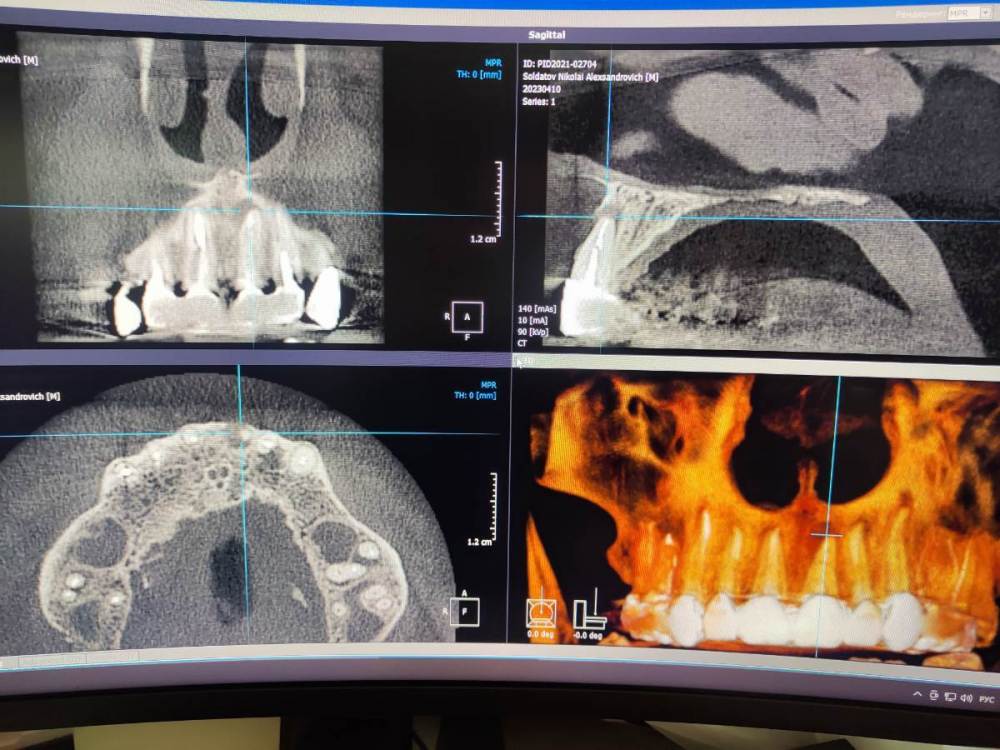

Nake Опубликовано 12 сентября, 2023 Поделиться Опубликовано 12 сентября, 2023 (изменено) Установили коронки. больше пол года ходил на временном цементе, как поставили на постоянный, спустя месяц появился шарик гноя на десне. Делали операцию с местной анестезией, не помогло. Врач сказал делать под общим надо что бы лучше почистить. Но на снимке кт, видно что коронка выпирает, неправильно установлено, на снимке с боку видно, и от этого труда что то попадает? Изменено 12 сентября, 2023 пользователем Nake Ссылка на комментарий

chervoncevdaniil Опубликовано 12 сентября, 2023 Поделиться Опубликовано 12 сентября, 2023 Причина не в коронках,а в том,что зуб с воспалением,за которым наблюдали на временном цементе дал обострение. К сожалению,это совпало с фиксацией на постоянный цемент 1 Ссылка на комментарий

chervoncevdaniil Опубликовано 12 сентября, 2023 Поделиться Опубликовано 12 сентября, 2023 Причина в любом случае не в фиксации постоянных коронок.,воспаление на корнях было задолго до и свищ от этого. Но суть дела это не меняет,инфекция в корневых каналах и с ней что то нужно делать(перелечивать каналы,делать резекцию верхушки корня или удалять и ставить имплант) 1 1 Ссылка на комментарий